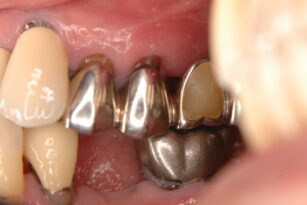

審美・補綴歯科

2025年12月26日

金属が気になる 30代 女性 セラミックインレーの症例